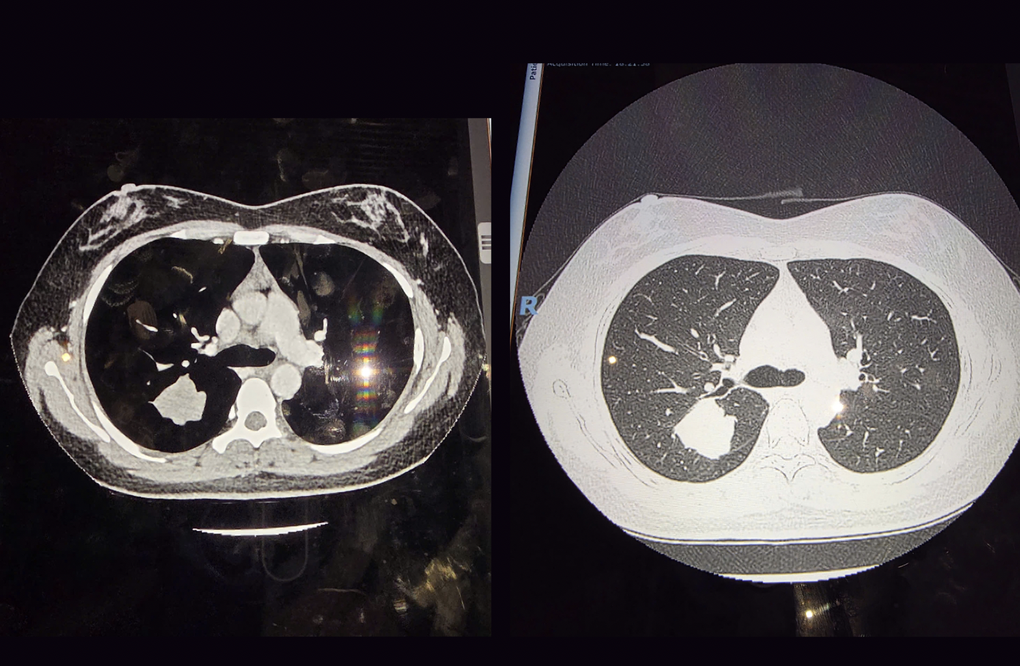

Một trường hợp phát hiện ung thư phổi từ kết quả chụp CT (Ảnh: BV).

ThS.BS Nguyễn Hữu Thanh, Trưởng khoa Chẩn đoán hình ảnh – Thăm dò chức năng của Bệnh viện Đa khoa Quốc tế Nam Sài Gòn cho biết, một nốt mờ qua CT sẽ là dấu hiệu gợi ý cho bác sĩ lên kế hoạch tầm soát theo dõi để đánh giá diễn tiến, đặc biệt là tốc độ tăng trưởng và đặc điểm hình ảnh.